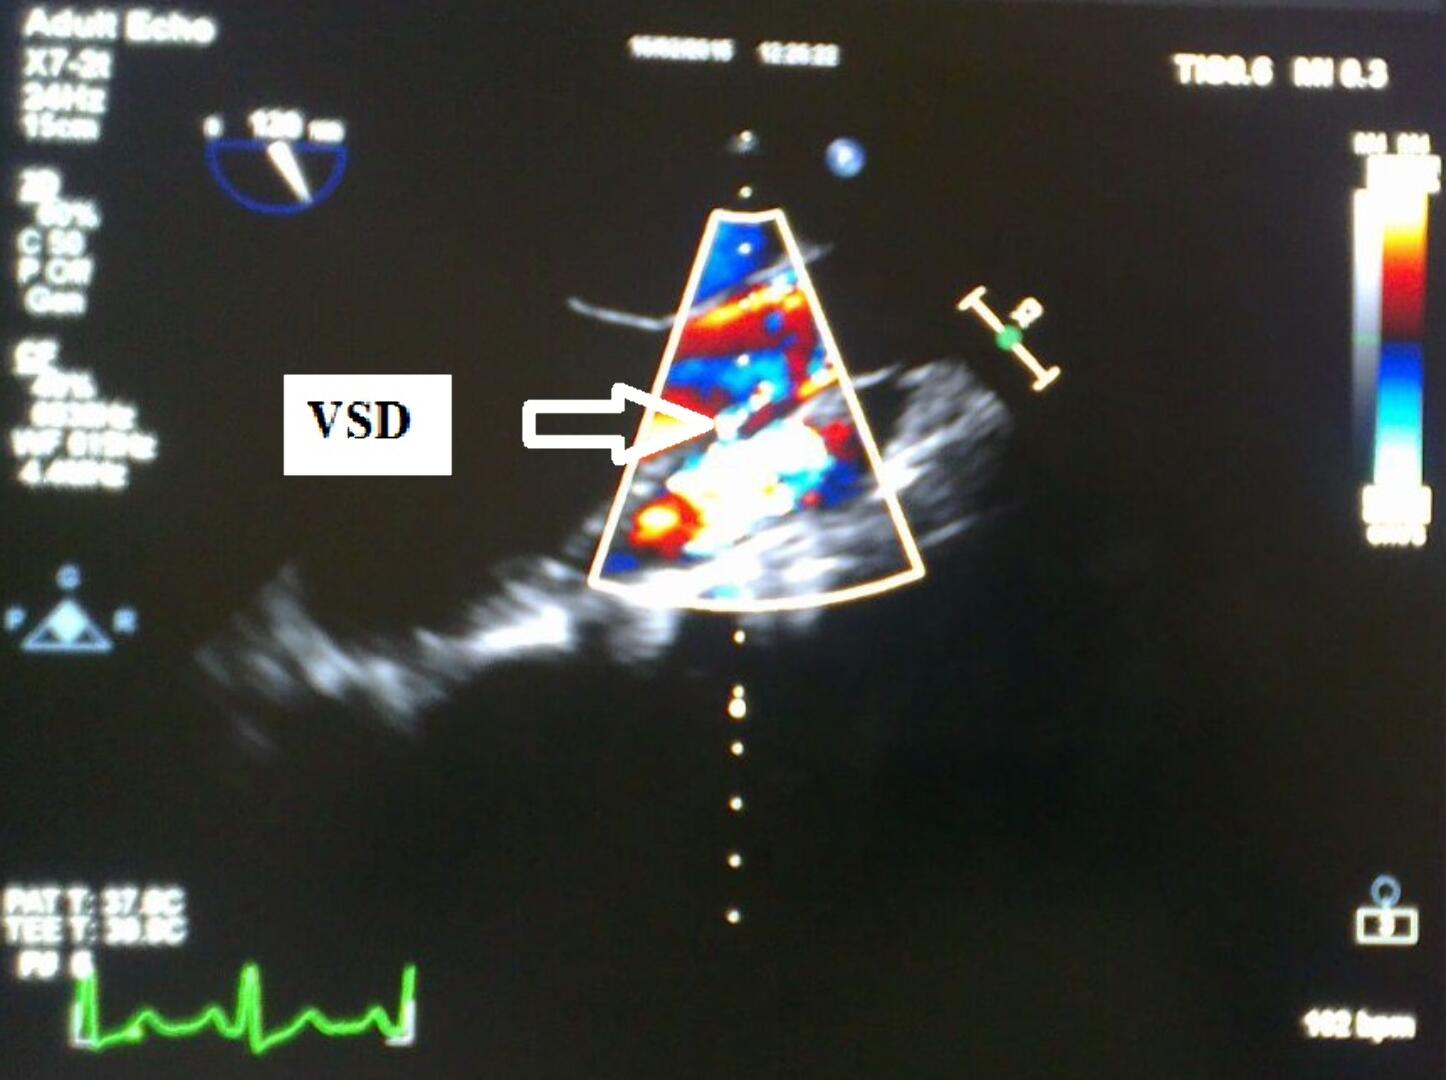

Kalp Deliği Kapalı Ameliyatla Tedavi Edildi